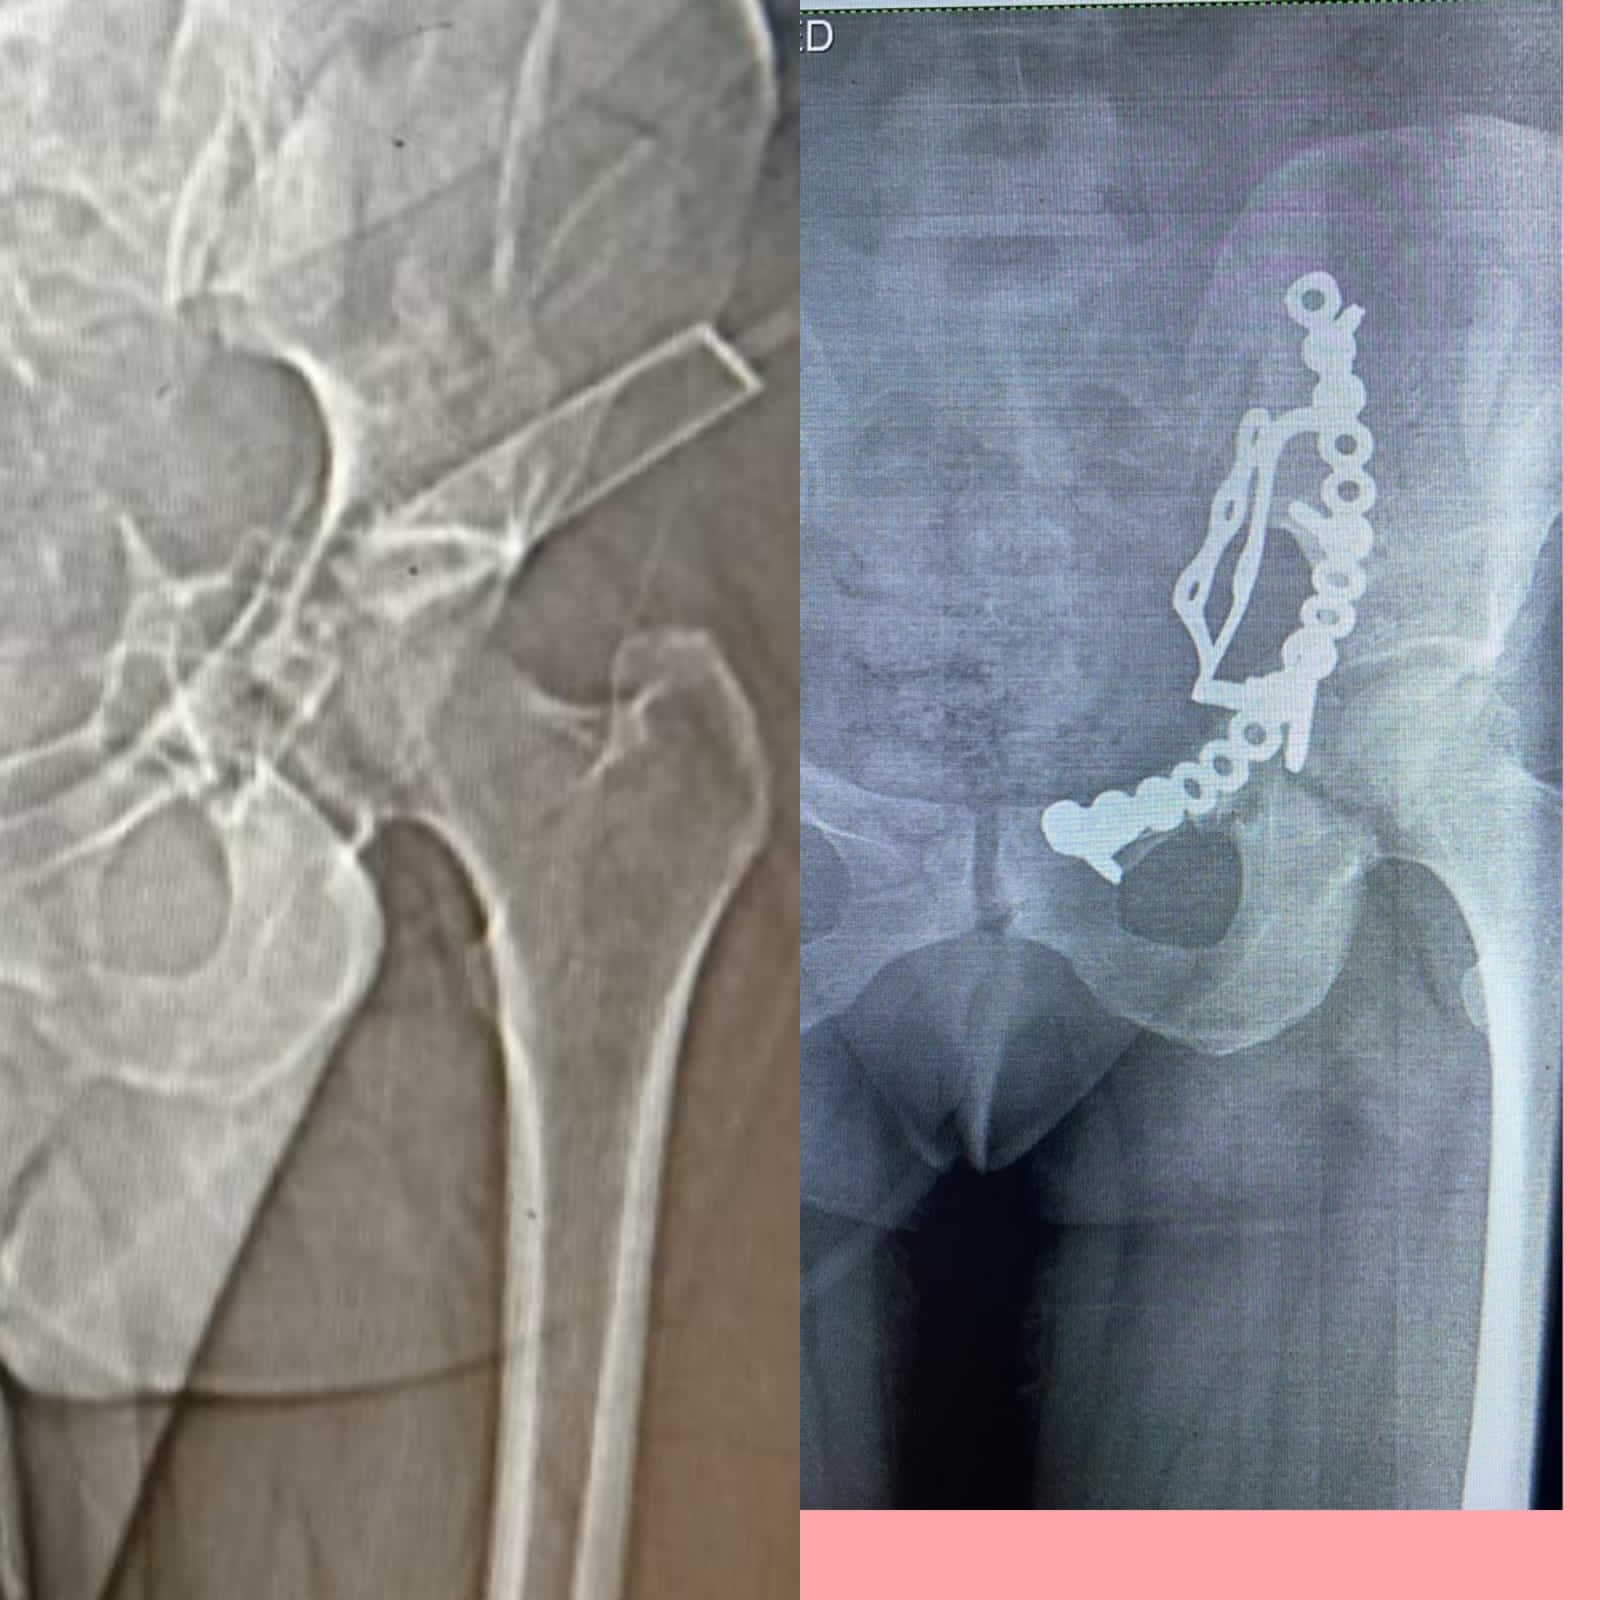

إجراء عملية إصلاح كسور متعددة مفتتة بالحوض لأول مرة بالشرقية

قال الدكتور هشام شوقي مسعود، وكيل وزارة الصحة بمحافظة الشرقية، إن الفريق الطبي بقسم جراحة العظام بمستشفى أبو حماد المركزي، أجرى عملية إصلاح كسور متعددة مفتتة بعظام الحوض لـ سيدة، وذلك للمرة الأولى.

وأوضح وكيل الوزارة، في بيانٍ له، قبل قليل، أنه تم إجراء عملية إصلاح الكسور المتعددة المفتتة بعظام الحوض للسيدة تحت إشراف مدير مستشفى أبو حماد المركزي، إذ تم إجراء عملية رد مفتوح مع تثبيت داخلي لكسر مفتت بالحق الحرقفي لـ عظم الحوض للسيدة، وذلك من خلال جراحة فتح البطن والحوض باستخدام شريحة من نوع خاص تحت مُخدر عام بغرفة العمليات بمستشفى أبو حماد المركزي.

وأشار وكيل وزارة الصحة بمحافظة الشرقية، إلى أن العملية التي أجريت تُعد ذات طابع خاص، وذلك بعد دخول المريضة قسم الاستقبال والطوارئ بمستشفى أبو حماد المركزي، إثر ادعاء حادث مروري، منوهًا بأنه تم إجراء كافة الفحوصات اللازمة، وتبين إصابة المريضة بجرح بالمثانة نتج عنه بول دموي ووجود كسر مفتت بالحق الحرقفي لعظم الحوض، قبل أن يشير إلى إجراء العملية، وأن المريضة الآن في حالة جيدة ومستقرة تحت متابعة الأطباء بمستشفى أبو حماد المركزي.